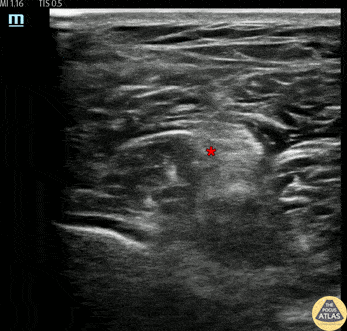

30s M presented with a nailgun injury after he unintentionally fired a nailgun into his booted foot. To facilitate removal, a popliteal sciatic nerve block was performed. The block is shown here, where a 20g block needle was advanced using in-plane guidance until the needle tip was visualized adjacent to the sciatic nerve. Anesthetic spread was visualized within Vloka’s sheath, the nerve sheath which encompasses the sciatic nerve as well as its branches (common peroneal and tibial nerves). A total of 20cc of anesthetic was injected. The patient had complete resolution of his pain shortly thereafter, and the nail was able to be removed without difficulty. Dr. Brigit Noon, PGY3 Denver Health Residency in Emergency Medicine